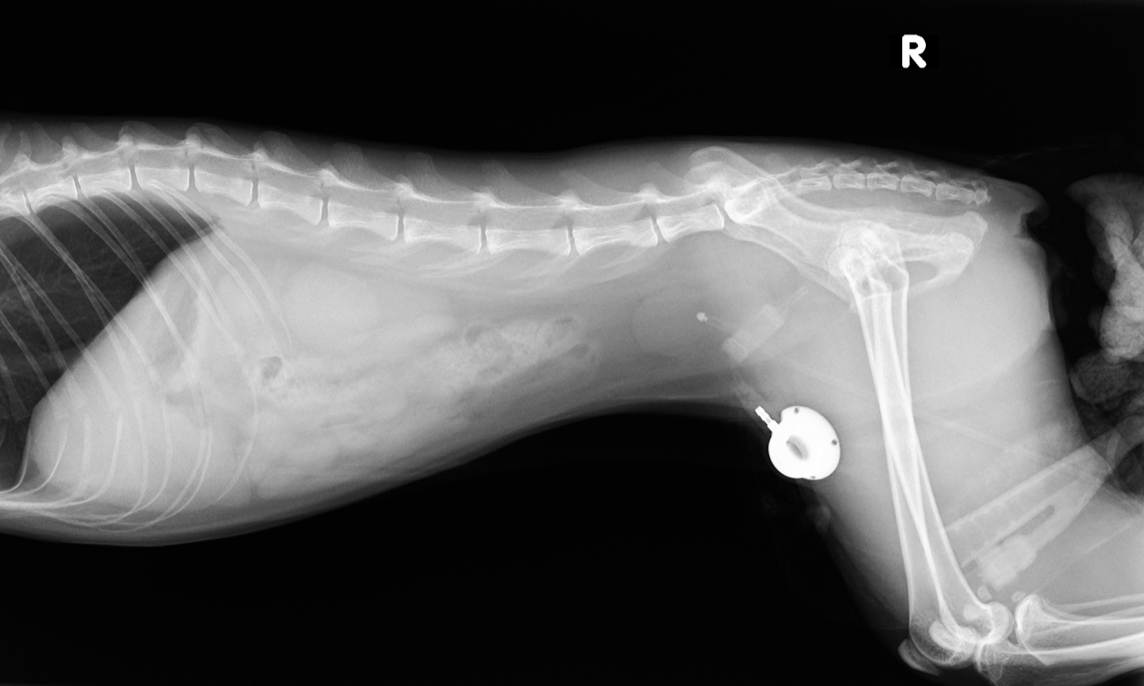

画像検査では、腹部X線で膀胱は小さく正常位置に確認され、超音波検査で尿道の肥厚および不整を認めた。

さらに手術計画のため実施した造影CTでは、尿路結石や明らかな解剖学的異常を認めず、既往手術の影響として腹腔内尿道は短縮(約11 mm)し、形状不整であることが明らかとなった。

手術は、術前CT評価後(day 76)に実施した。麻酔はアトロピン0.04 mg/kg SC、フェンタニル2.5 µg/kg IVで前投与し、プロポフォール6 mg/kg IVで導入、イソフルラン1.4–1.8%で維持した(ETT 4.5 mm)。周術期はドパミンCRI(2.5–5.0 µg/kg/min)およびフェンタニルCRI(1.25–10 µg/kg/h)で循環・鎮痛を調整し、アンピシリン20 mg/kg IVを投与した。術式は正中切開で開腹し、癒着剥離後に膀胱頭側へstay sutureを設置したうえで、10 mm HO(LePort;cuff幅7 mm・厚さ2 mm)を膀胱尾側の尿道周囲に設置し、3-0 polypropyleneで固定した。アクセス・ポートは大腿筋膜へ4-0 polypropyleneで固定した。システムを生理食塩水でプライミング後、0.5 mL注入で尿道閉塞を確認して抜去し、閉腹後は尿焼け管理のため尿道カテーテルを留置した。手術時間は80分で、術後回復は良好だった。